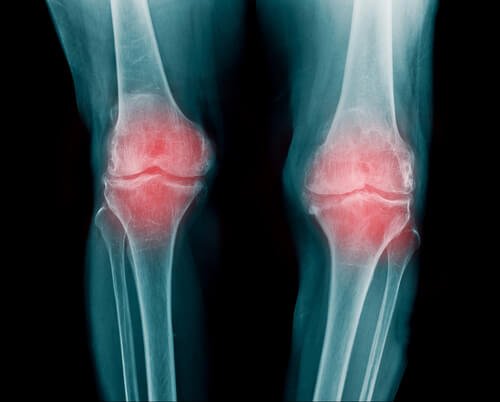

Rheumatoid arthritis

- Reumatoid arthritis er en betændelse i dine led. Det kan påvirke flere forskellige led ad gangen. Generelt ses det i fingre, arme og knæ.

- Personer med reumatoid arthritis vil opleve nedsat mobilitet. Efter den prikkende fornemmelse, begynder værre smerter oftest over tid.

- Dette sker i takt med at kalciumaflejringer ophobes i leddene. I begyndelsen kommer den prikkende følelse, men i det at brusken svækkes og gradvist nedbrydes, vil det forårsage en smerte der kun vil blive værre over tid.

- Man ser oftest reumatoid arthritis i håndled, fingre og knæ. Det kan dog også påvirke andre led. Denne sygdom er forbundet med slidgigt og andre lidelser relateret til skjoldbruskkirtlen.